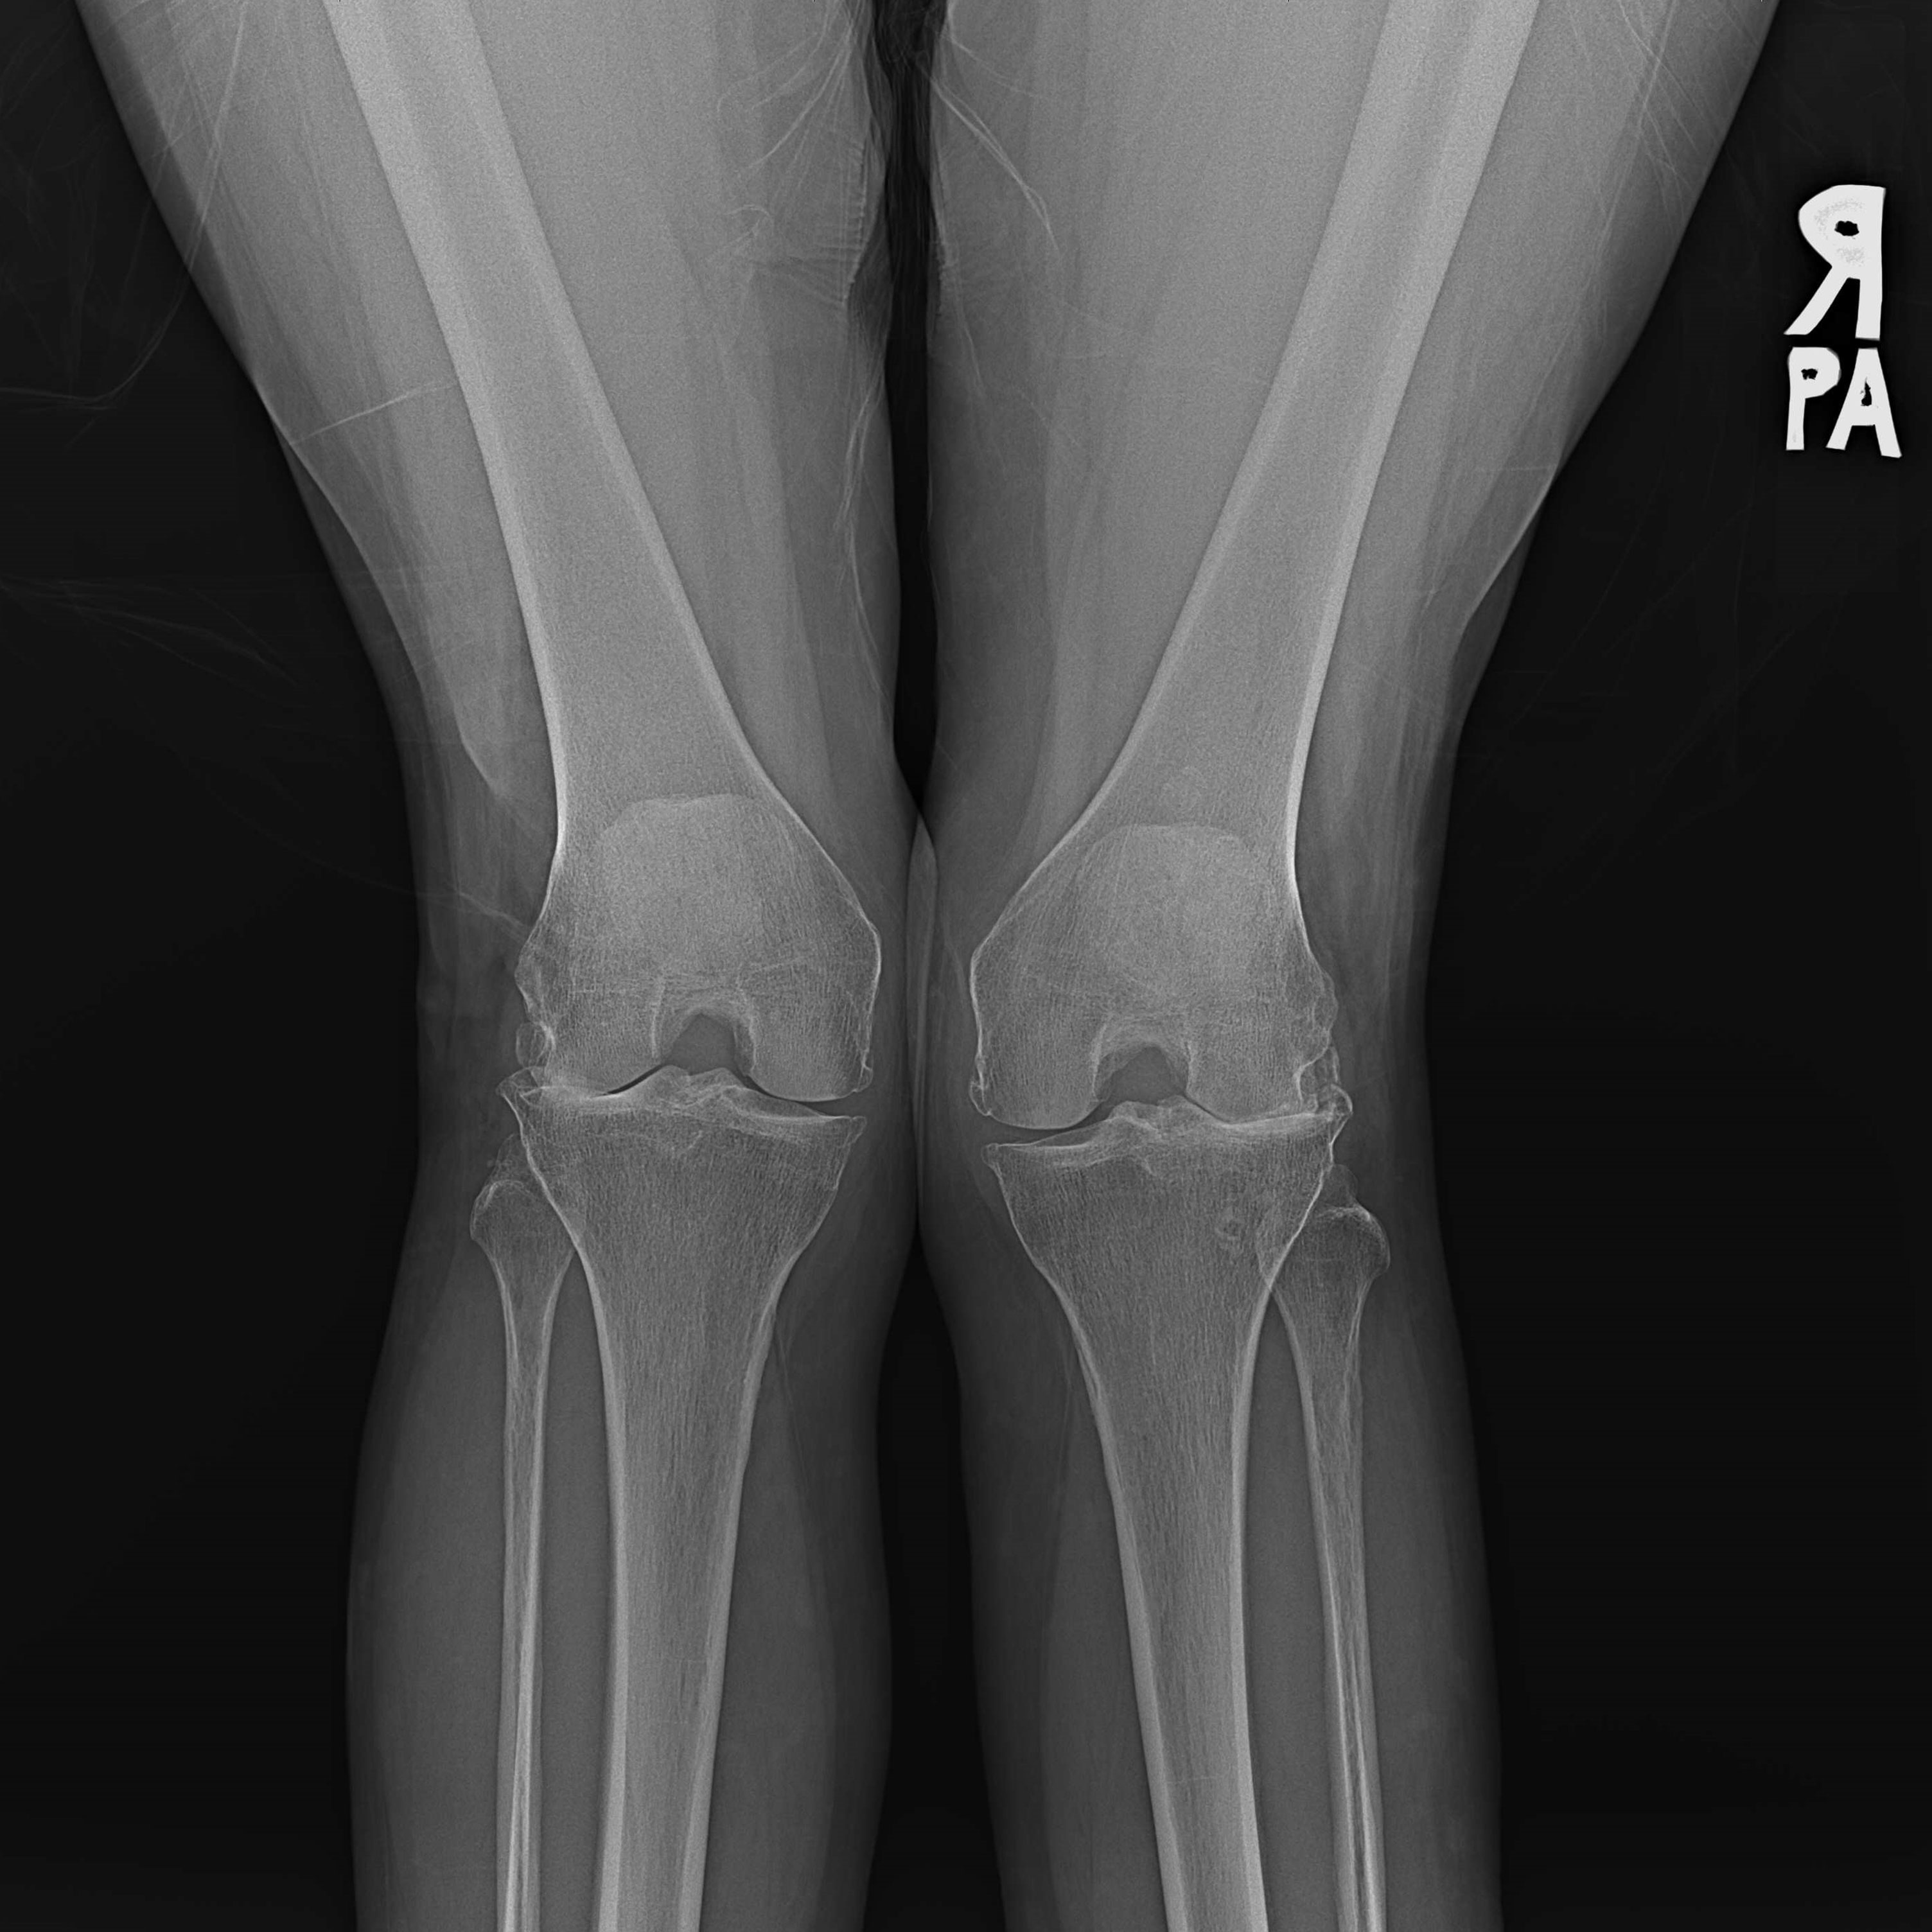

傳統全膝關節置換 首頁 案例分享 膝關節手術 傳統全膝關節置換 江女士 61歲 術前 術後 劉先生 83歲 術前 術後 70歲 柯先生 術前 術後 75歲 黃女士 術前 術後 77歲 羅女士 術前 術後